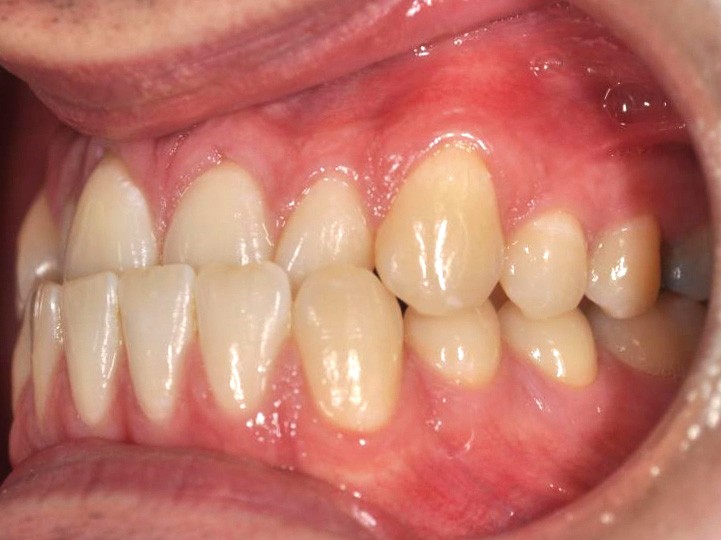

En intra-arcades (fig. 4-6), on note une classe III molaire et canine (fig. 4-5), trois plans d’occlusion, une déviation des milieux d’origine mandibulaire et un inversé articulé du bloc incisif maxillaire ; le biotype parodontal est fin, et l’on note des récessions gingivales (12, 13, 23, 33, 43) certainement dues à la mauvaise position et aux forces mal réparties lors de la mastication (fig. 5). L’arcade maxillaire est carrée avec une DDM antérieure (fig. 7), l’arcade mandibulaire étroite et allongée (fig. 8).